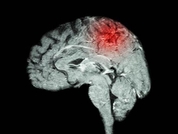

날씨가 급격히 추워진 겨울철에는 혈관이 수축하고 혈압이 올라가 뇌졸중 발생 위험이 커진다. 전문가들은 겨울철 뇌졸중 예방을 위해 장시간 실외에서 활동하는 것을 자제하고 방한용품을 착용하는 한편, 증상이 생기면 곧바로 병원을 찾아 치료받아야 한다고 조언한다. 3일 건강보험심사평가원의 '뇌혈관질환 진료 현황'에 따르면 뇌졸중 환자는 ▲ 2018년 59만1천946명 ▲ 2019년 61만776명 ▲ 2020년 60만2천161명 ▲ 2021년 62만504명 ▲ 2022년 63만4천177명으로 증가하는 추세다. 2022년 기준 뇌졸중 진료를 많이 받은 연령대는 70대(19만5천608명), 60대(17만4천109명), 80세 이상(16만6천978명) 순으로 집계돼 고령 환자에게 주의가 필요한 것으로 나타났다. 뇌졸중은 크게 뇌경색(허혈성 뇌졸중)과 뇌출혈(출혈성 뇌졸중)로 나뉜다. 뇌경색은 뇌혈관이 좁아지거나 막혀 뇌로 혈액이 충분히 공급되지 않아 생기고, 뇌출혈은 뇌혈관이 팽창해 터지면서 발생한다. 박무석 이대서울병원 신경과 교수는 "뇌졸중은 증상이 갑작스럽게 나타나기 때문에 겨울철에는 불필요한 실외 활동을 줄이고 외출할 때 따뜻한 옷과 장갑 등으로 체온을 유지해야 한